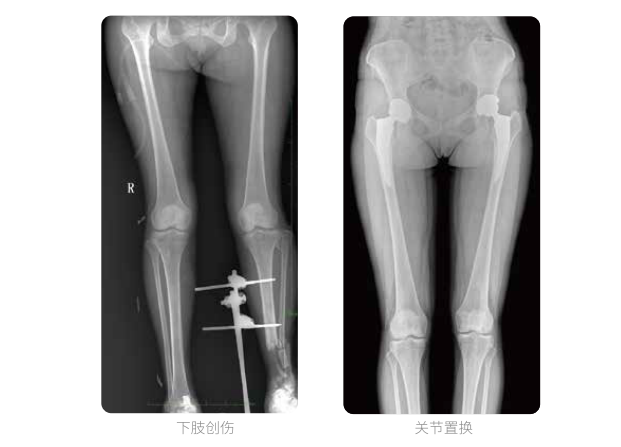

雙下肢臨床影像

普愛醫療動態數字化X線攝影(動態DR)可以整體顯示雙髖至雙踝關節,直觀的展示因關節軟骨磨損和軟組織不平衡所造成的畸形及力線異常,全面對比了解雙下肢的病變情況。對于下肢矯正和人工關節置換術的術前計劃,術后觀察有著重要的臨床意義。

普愛醫療動態數字化X線攝影(動態DR)一次成像不拼接,解決了拼接圖像存在密度不均勻,拼接處圖像配準和放大效應等問題,給臨床帶來了真正的大視野影像解決方案,高清畫質,準確成像不失真,輔助醫生準確診斷疾病。